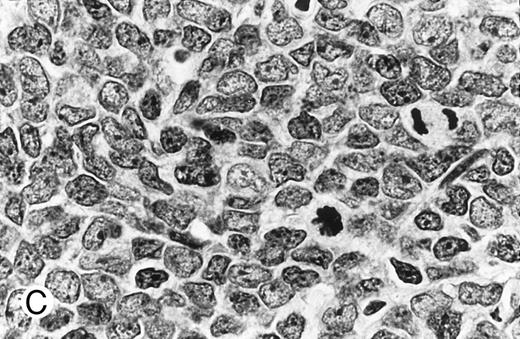

Cytologically, MCL nuclei were round to ovoid, slightly irregular with inconspicuous nucleoli and slightly clumped chromatin (Fig 3A). Cytoplasm was scant. Larger cells with medium-sized nuclei, fine chromatin, inconspicuous nucleoli, and scant cytoplasm were present in most cases to varying degrees. These cells resembled lymphoblasts rather than large noncleaved cells, prolymphocytes, or paraimmunoblasts. In some cases, lymphoblast-like cells were present in significantly increased numbers (Figs 3B and C), implying cytologic transformation (discussed below). Mitoses were easily found in the majority of cases, the prognostic significance of which is discussed below.

Composite photograph showing the cytologic features of MCL. (A) Typical cytology of MCL characterized by cells with small, slightly irregular nuclei, inconspicuous nucleoli, and minimal cytoplasm. Note the frequent epithelioid histiocytes (arrows). (B) MCL with prominent features of transformation, but not clearly blastic. Increased numbers of larger cells with fine chromatin and inconspicuous nucleoli are shown (arrows). (C) Blastic MCL. Note the cytologic resemblance to lymphoblastic lymphoma. (D) OS of 80 patients with MCL based on the presence of blastic features. The 5 cases designated as blastic MCL were associated with a significantly shorter survival when compared with that of all others (n = 75) including those with features of transformation as shown in (B).

Blastic features.Virtually all 80 cases had at least a few cells with larger nuclei, finer chromatin, and inconspicuous nucleoli; however, in the majority of cases, these cells were present in small numbers. When present in increased numbers, these lymphoblast-like cells were almost always accompanied by an increase in mitotic activity and, occasionally, the presence of tingible body macrophages (Fig 3B). These cases were designated as having prominent features of cytologic transformation. In a minority (n = 5), the blastic cells were so numerous that the histology was nearly indistinguishable from that of lymphoblastic lymphoma; these cases were designated blastic MCL (Fig 3C). The mean MS in the blastic MCL cases was 57.

The OS was significantly shorter for those cases with blastic morphology (Fig 3D). No statistically significant differences in survival were observed between the 16 cases that were transformed to some degree but not truly blastic and the remaining 59 cases that showed no evidence of transformation.